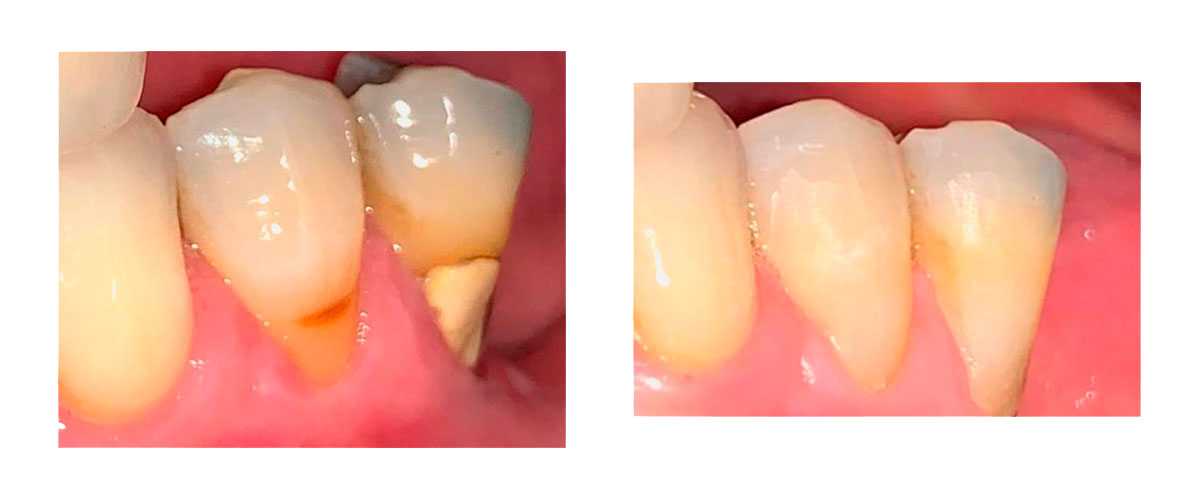

• ⦿ En la medida que sea posible buscamos armonizar la mordida: Si faltan piezas dentarias, reemplazarlas, si es necesario un tratamiento de ortodoncia hacerlo, si hay que hacer desgastes selectivos, hacerlos, lograr que los dientes no obliguen a las articulaciones a trabajar en una posición incómoda.

• ⦿ Devolver estructuras perdidas. Tanto devolver piezas ausentes como recuperar la dimensión vertical y los niveles de oclusión que hayan perdido las piezas dentarias por el desgaste.